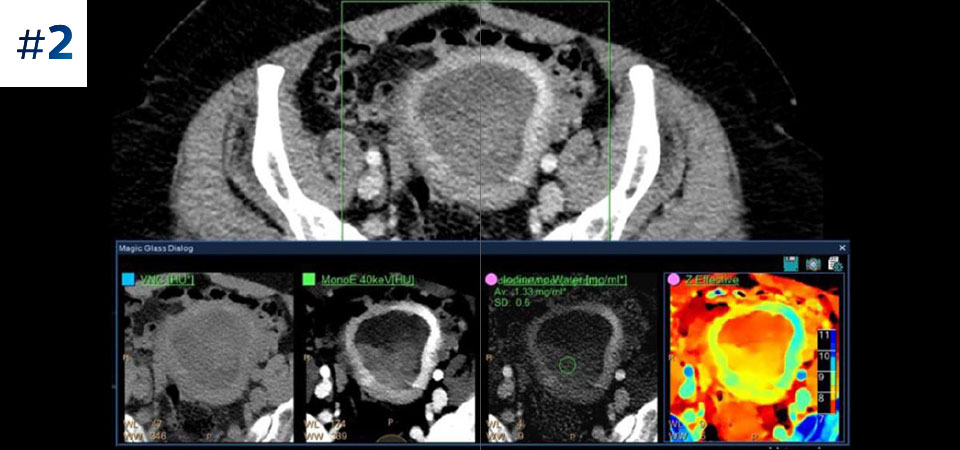

Vá além da CT convencional. Veja de que forma os vários tipos de resultados obtidos com deteção espectral podem aumentar a fiabilidade do seu diagnóstico.

Conheça a diferença entre a CT com detetor espectral e a CT convencional